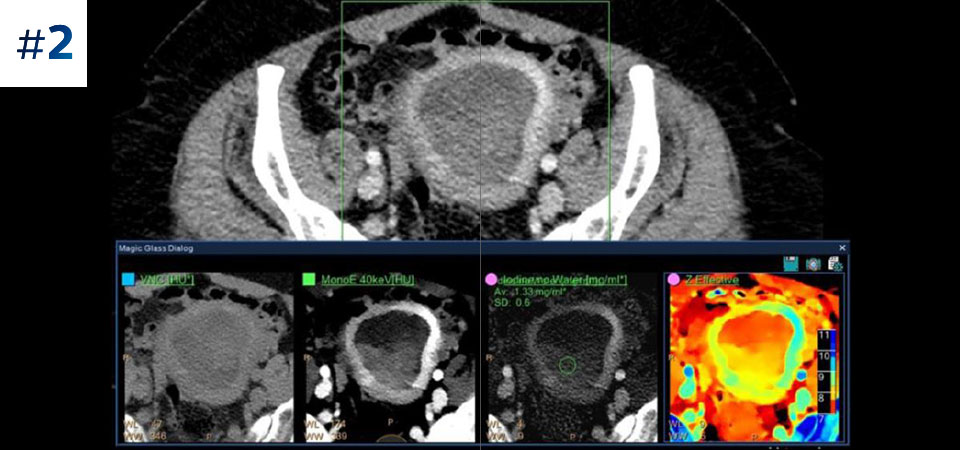

Reduced follow-up exams Improved tissue characterization and visualization may reduce the need for follow-up scanning for sub-optimal exams and incidental findings.